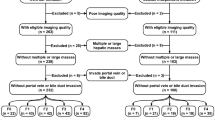

One hundred twenty-eight patients underwent a 99mTc-GSA SPECT/CT-based liver function evaluation. All were classified into the low liver-damage or high liver-damage group. Four clinical (age, sex, background liver disease and histological type) and 8 quantitative 99mTc-GSA SPECT/CT features (receptor index [LHL15], clearance index [HH15], liver-SUVmax, liver-SUVmean, heart-SUVmax, metabolic volume of liver [MVL], total lesion GSA [TL-GSA, liver-SUVmean × MVL] and SUVmax ratio [liver-SUVmax/heart-SUVmax]) were obtained. To predict high liver damage, a machine learning classification with features selection based on Gini impurity and principal component analysis (PCA) were performed using a support vector machine and a random forest (RF) with a five-fold cross-validation scheme. To overcome imbalanced data, stratified sampling was used. The ability to predict high liver damage was evaluated using a receiver operating characteristic (ROC) curve analysis.

Four indices (LHL15, HH15, heart SUVmax and SUVmax ratio) yielded high areas under the ROC curves (AUCs) for predicting high liver damage (range: 0.89–0.93). In a machine learning classification, the RF with selected features (heart SUVmax, SUVmax ratio, LHL15, HH15, and background liver disease) and PCA model yielded the best performance for predicting high liver damage (AUC = 0.956, sensitivity = 96.3%, specificity = 90.0%, accuracy = 91.4%).